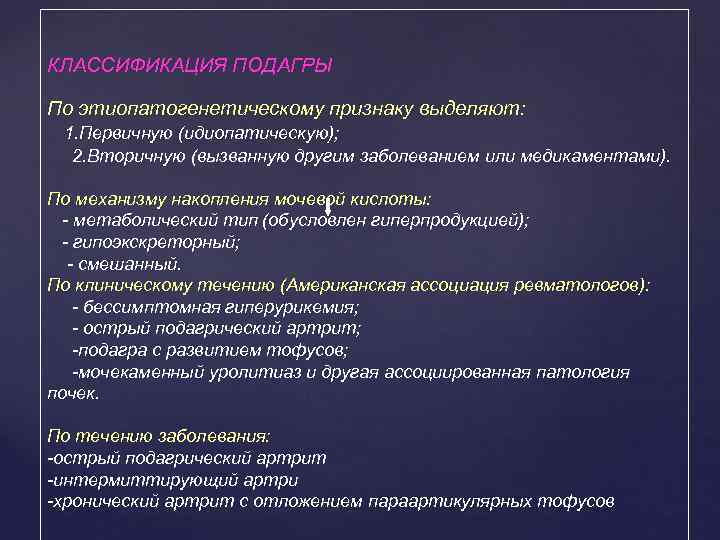

КЛАССИФИКАЦИЯ ПОДАГРЫ По этиопатогенетическому признаку выделяют: 1. Первичную (идиопатическую); 2. Вторичную (вызванную другим заболеванием или медикаментами). По механизму накопления мочевой кислоты: - метаболический тип (обусловлен гиперпродукцией); - гипоэкскреторный; - смешанный. По клиническому течению (Американская ассоциация ревматологов): - бессимптомная гиперурикемия; - острый подагрический артрит; -подагра с развитием тофусов; -мочекаменный уролитиаз и другая ассоциированная патология почек. По течению заболевания: -острый подагрический артрит -интермиттирующий артри -хронический артрит с отложением параартикулярных тофусов

КЛАССИФИКАЦИЯ ПОДАГРЫ По этиопатогенетическому признаку выделяют: 1. Первичную (идиопатическую); 2. Вторичную (вызванную другим заболеванием или медикаментами). По механизму накопления мочевой кислоты: - метаболический тип (обусловлен гиперпродукцией); - гипоэкскреторный; - смешанный. По клиническому течению (Американская ассоциация ревматологов): - бессимптомная гиперурикемия; - острый подагрический артрит; -подагра с развитием тофусов; -мочекаменный уролитиаз и другая ассоциированная патология почек. По течению заболевания: -острый подагрический артрит -интермиттирующий артри -хронический артрит с отложением параартикулярных тофусов